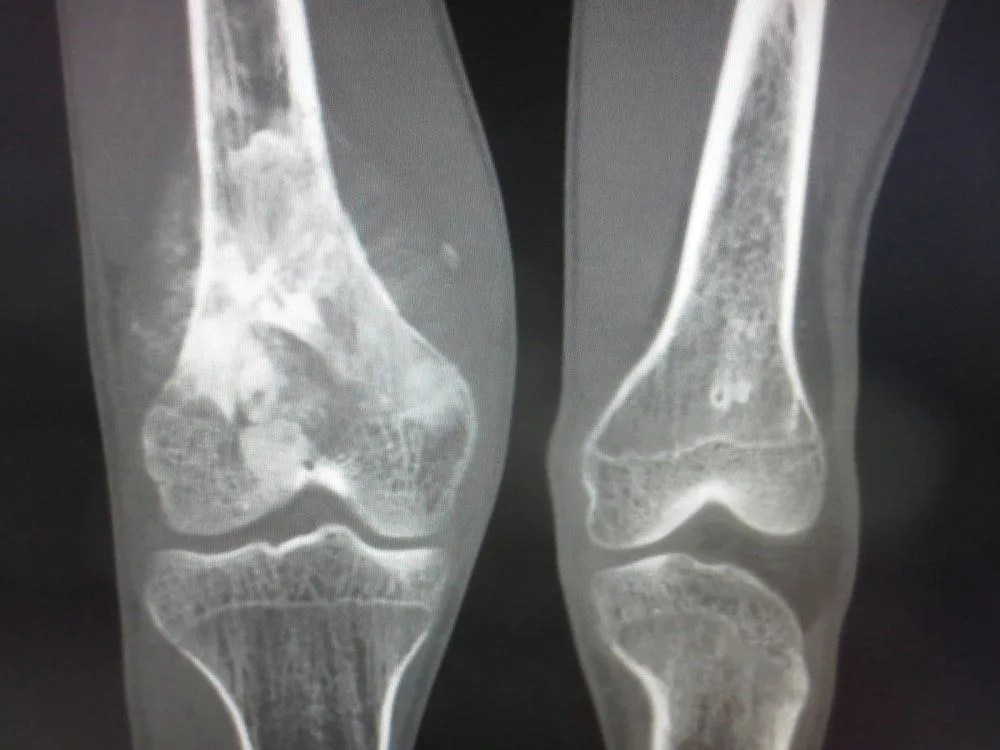

Besaran biaya yang dibutuhkan untuk melakukan ct scan bervariasi tergantung dari rumah sakit, kelas perawatan, dan bagian tubuh yang akan diperiksa. Kanker Tulang Penyebab Gejala Hingga Pengobatan

Kanker Tulang Penyebab Gejala Hingga Pengobatan from cdn.hellosehat.com